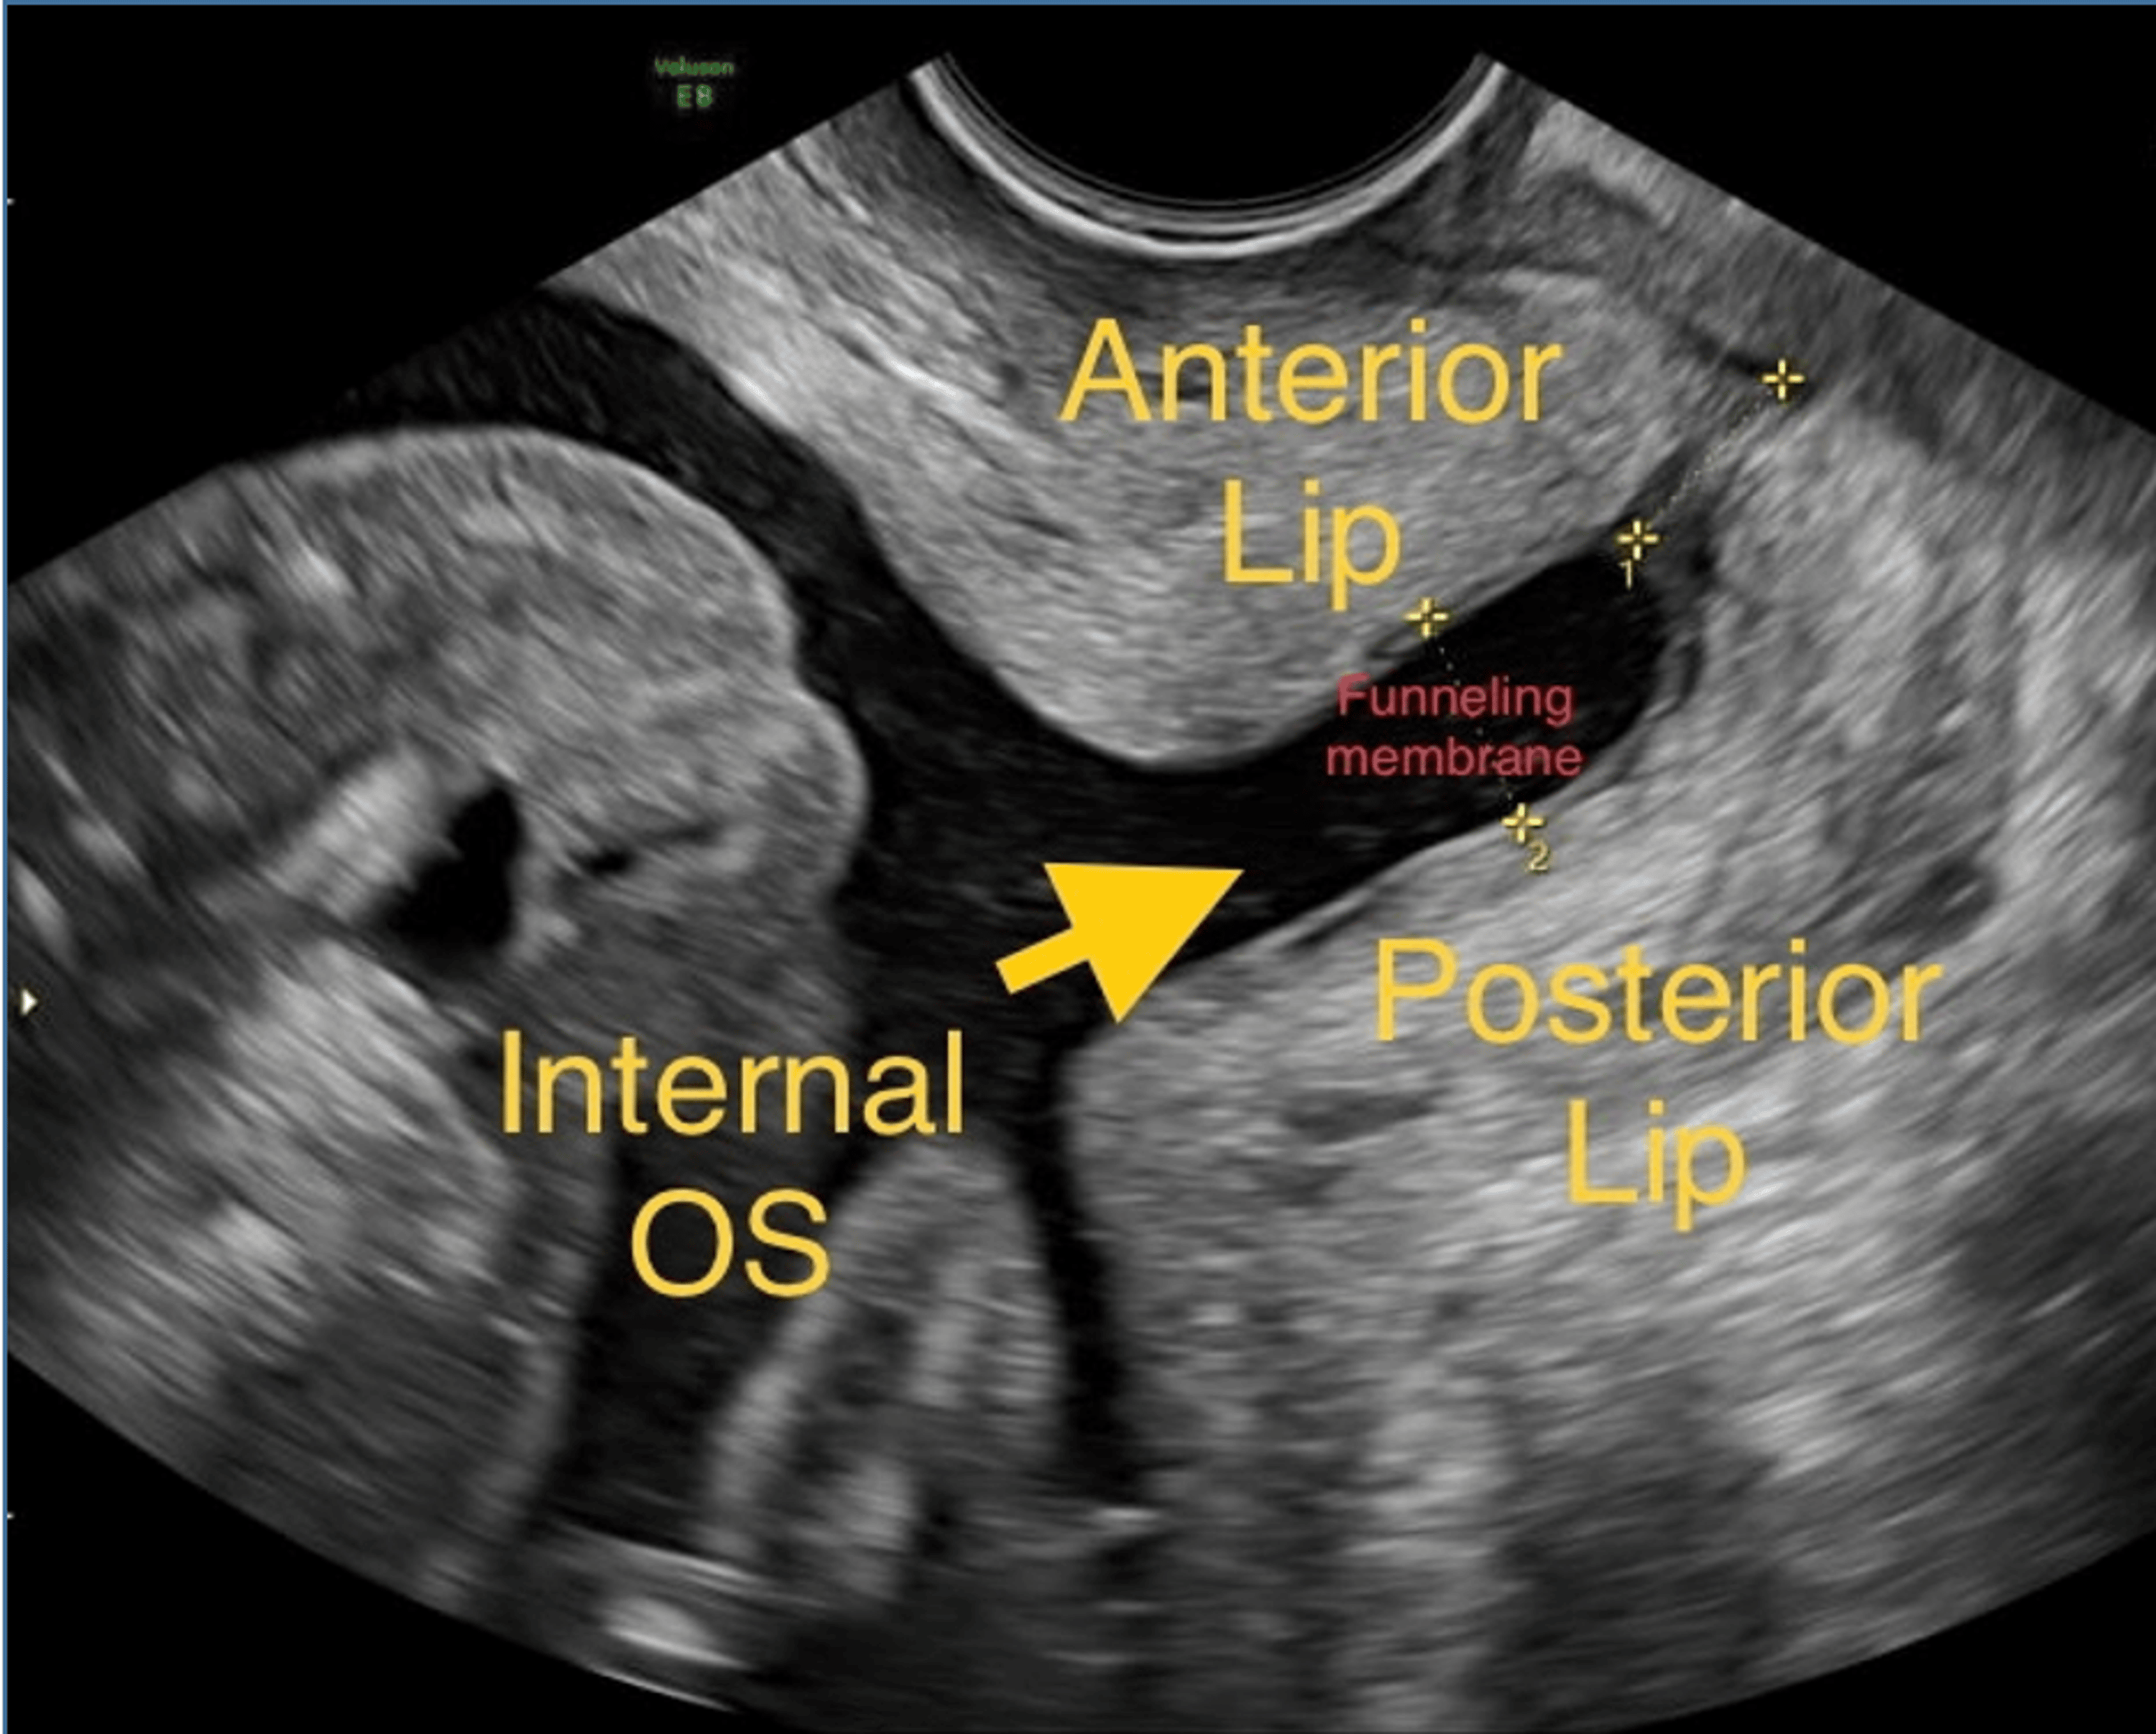

Cervical Funneling on ultrasound YouTube Short Cervix On Ultrasound  Many clinicians consider transvaginal ultrasound (tvu) a blessing; This consult provides guidance for. The cervix may be shortened because of progesterone. Midtrimester cervical length assessment using transvaginal ultrasound is one of the best clinical predictors of spontaneous preterm birth. Some would say it's the most important development. Since the goal is to keep your “bun in the oven” as long. Short Cervix On Ultrasound.